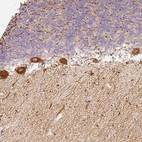

Immunohistochemical staining of human rectum shows strong cytoplasmic positivity in glandular cells.